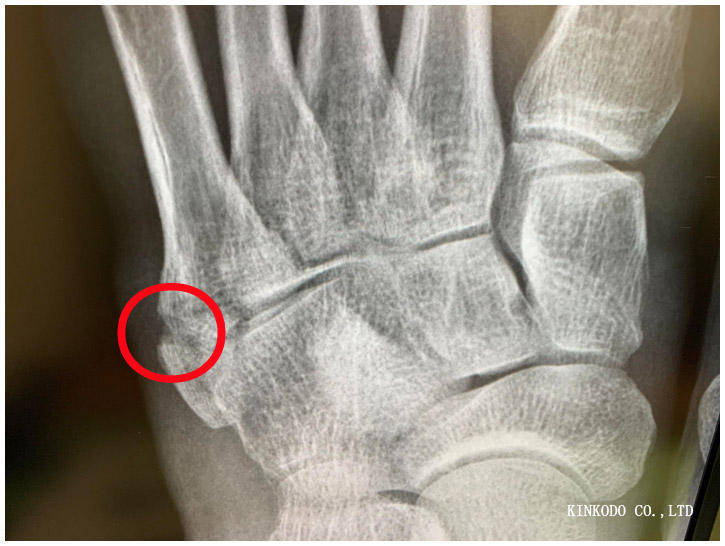

2021年10月13日に市営陸上競技場で足を捻って、左足の小指の付け根を下駄骨折しました。